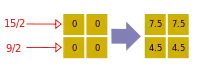

- A basic premise in back-projection is that any attenuation of the X-ray beam has occurred uniformly along the path followed from the source to the detector. Let's consider a simple tomographic slice containing just four voxels to illustrate the computational approach - see Figure 7.11. The first projection, P1 is obtained from a horizontal exposure from left to right in the figure. The back-projection of P1 involves putting the values 7 and 9 in both elements of the first and second rows, respectively. The second projection, P2 adds a 4 to the top right element, 1 to the bottom left element and 11 to the other two elements when it is back-projected. The other projections are treated in a similar fashion. Following regularisation of the data set the final image is obtained at the bottom left of the figure.